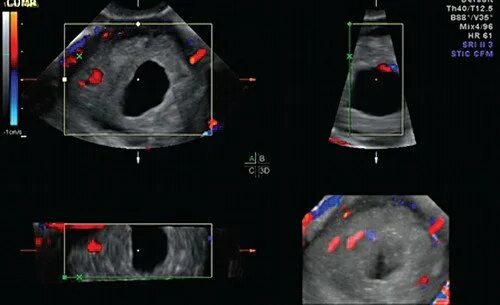

Локусы при цдк что это